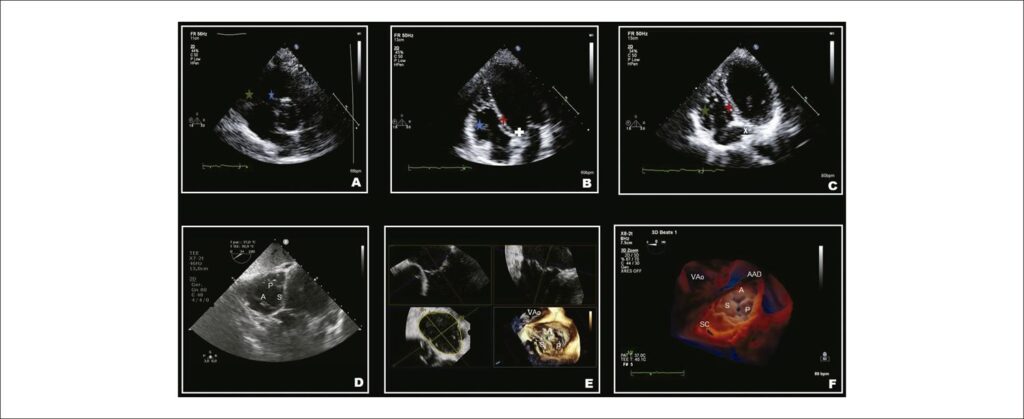

A regurgitação tricúspide (RT) importante está associada à alta morbidade e mortalidade. Como o tratamento cirúrgico da RT isolada tem sido associado à alta mortalidade, as intervenções transcateter na valva tricúspide (VT) têm sido utilizadas para o seu tratamento, com risco relativamente mais baixo. Há um atraso na intervenção da RT e provavelmente está relacionado a uma compreensão limitada da anatomia da VT e do ventrículo direito, além da subestimação da gravidade da RT. Nesse cenário, faz-se necessário o conhecimento anatômico abrangente da VT, a fisiopatologia envolvida no mecanismo de regurgitação, assim como a sua graduação mais precisa. A VT tem peculiaridades anatômica, histológica e espacial que fazem a sua avalição ser mais complexa, quando comparado à valva mitral, sendo necessário o conhecimento e treinamento nas diversas técnicas ecocardiográficas que serão utilizadas frequentemente em combinação para uma avaliação precisa.

Esta revisão descreverá a anatomia da VT, o papel do ecocardiograma no diagnóstico, graduação e fisiopatologia envolvida na RT, as principais opções atuais de tratamento transcateter da RT e a avaliação do resultado após intervenção transcateter por meio de múltiplas modalidades ecocardiográficas.